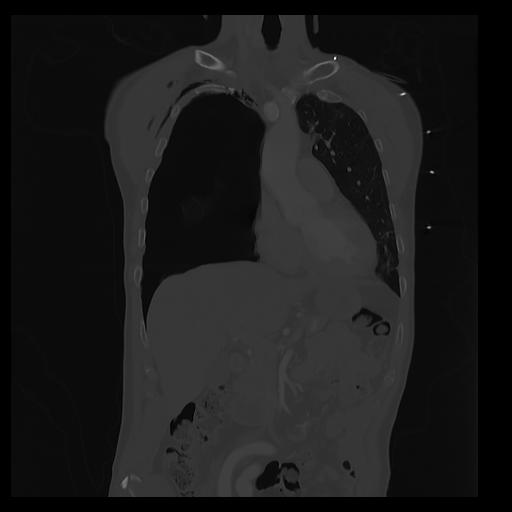

32 PULMON,CE,Coronal,3.000,PULMON,Coronal,